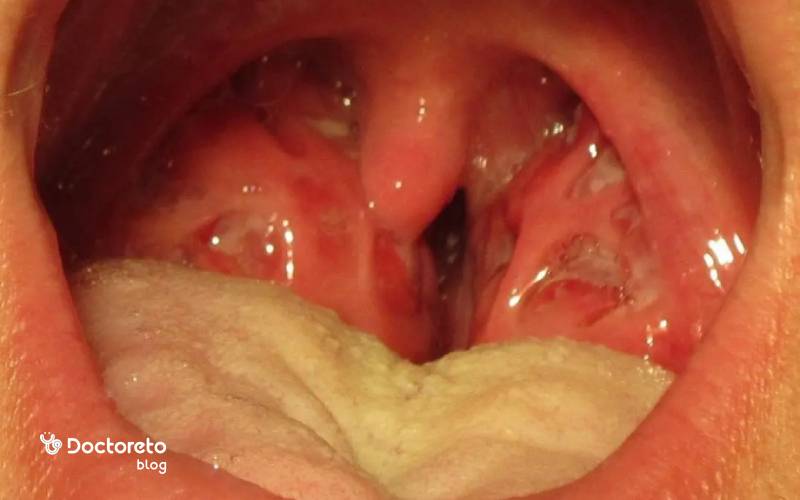

- قرمزی و ورم لوزهها و گلو

- وجود پوشش سفید، زرد یا خاکستری روی لوزهها